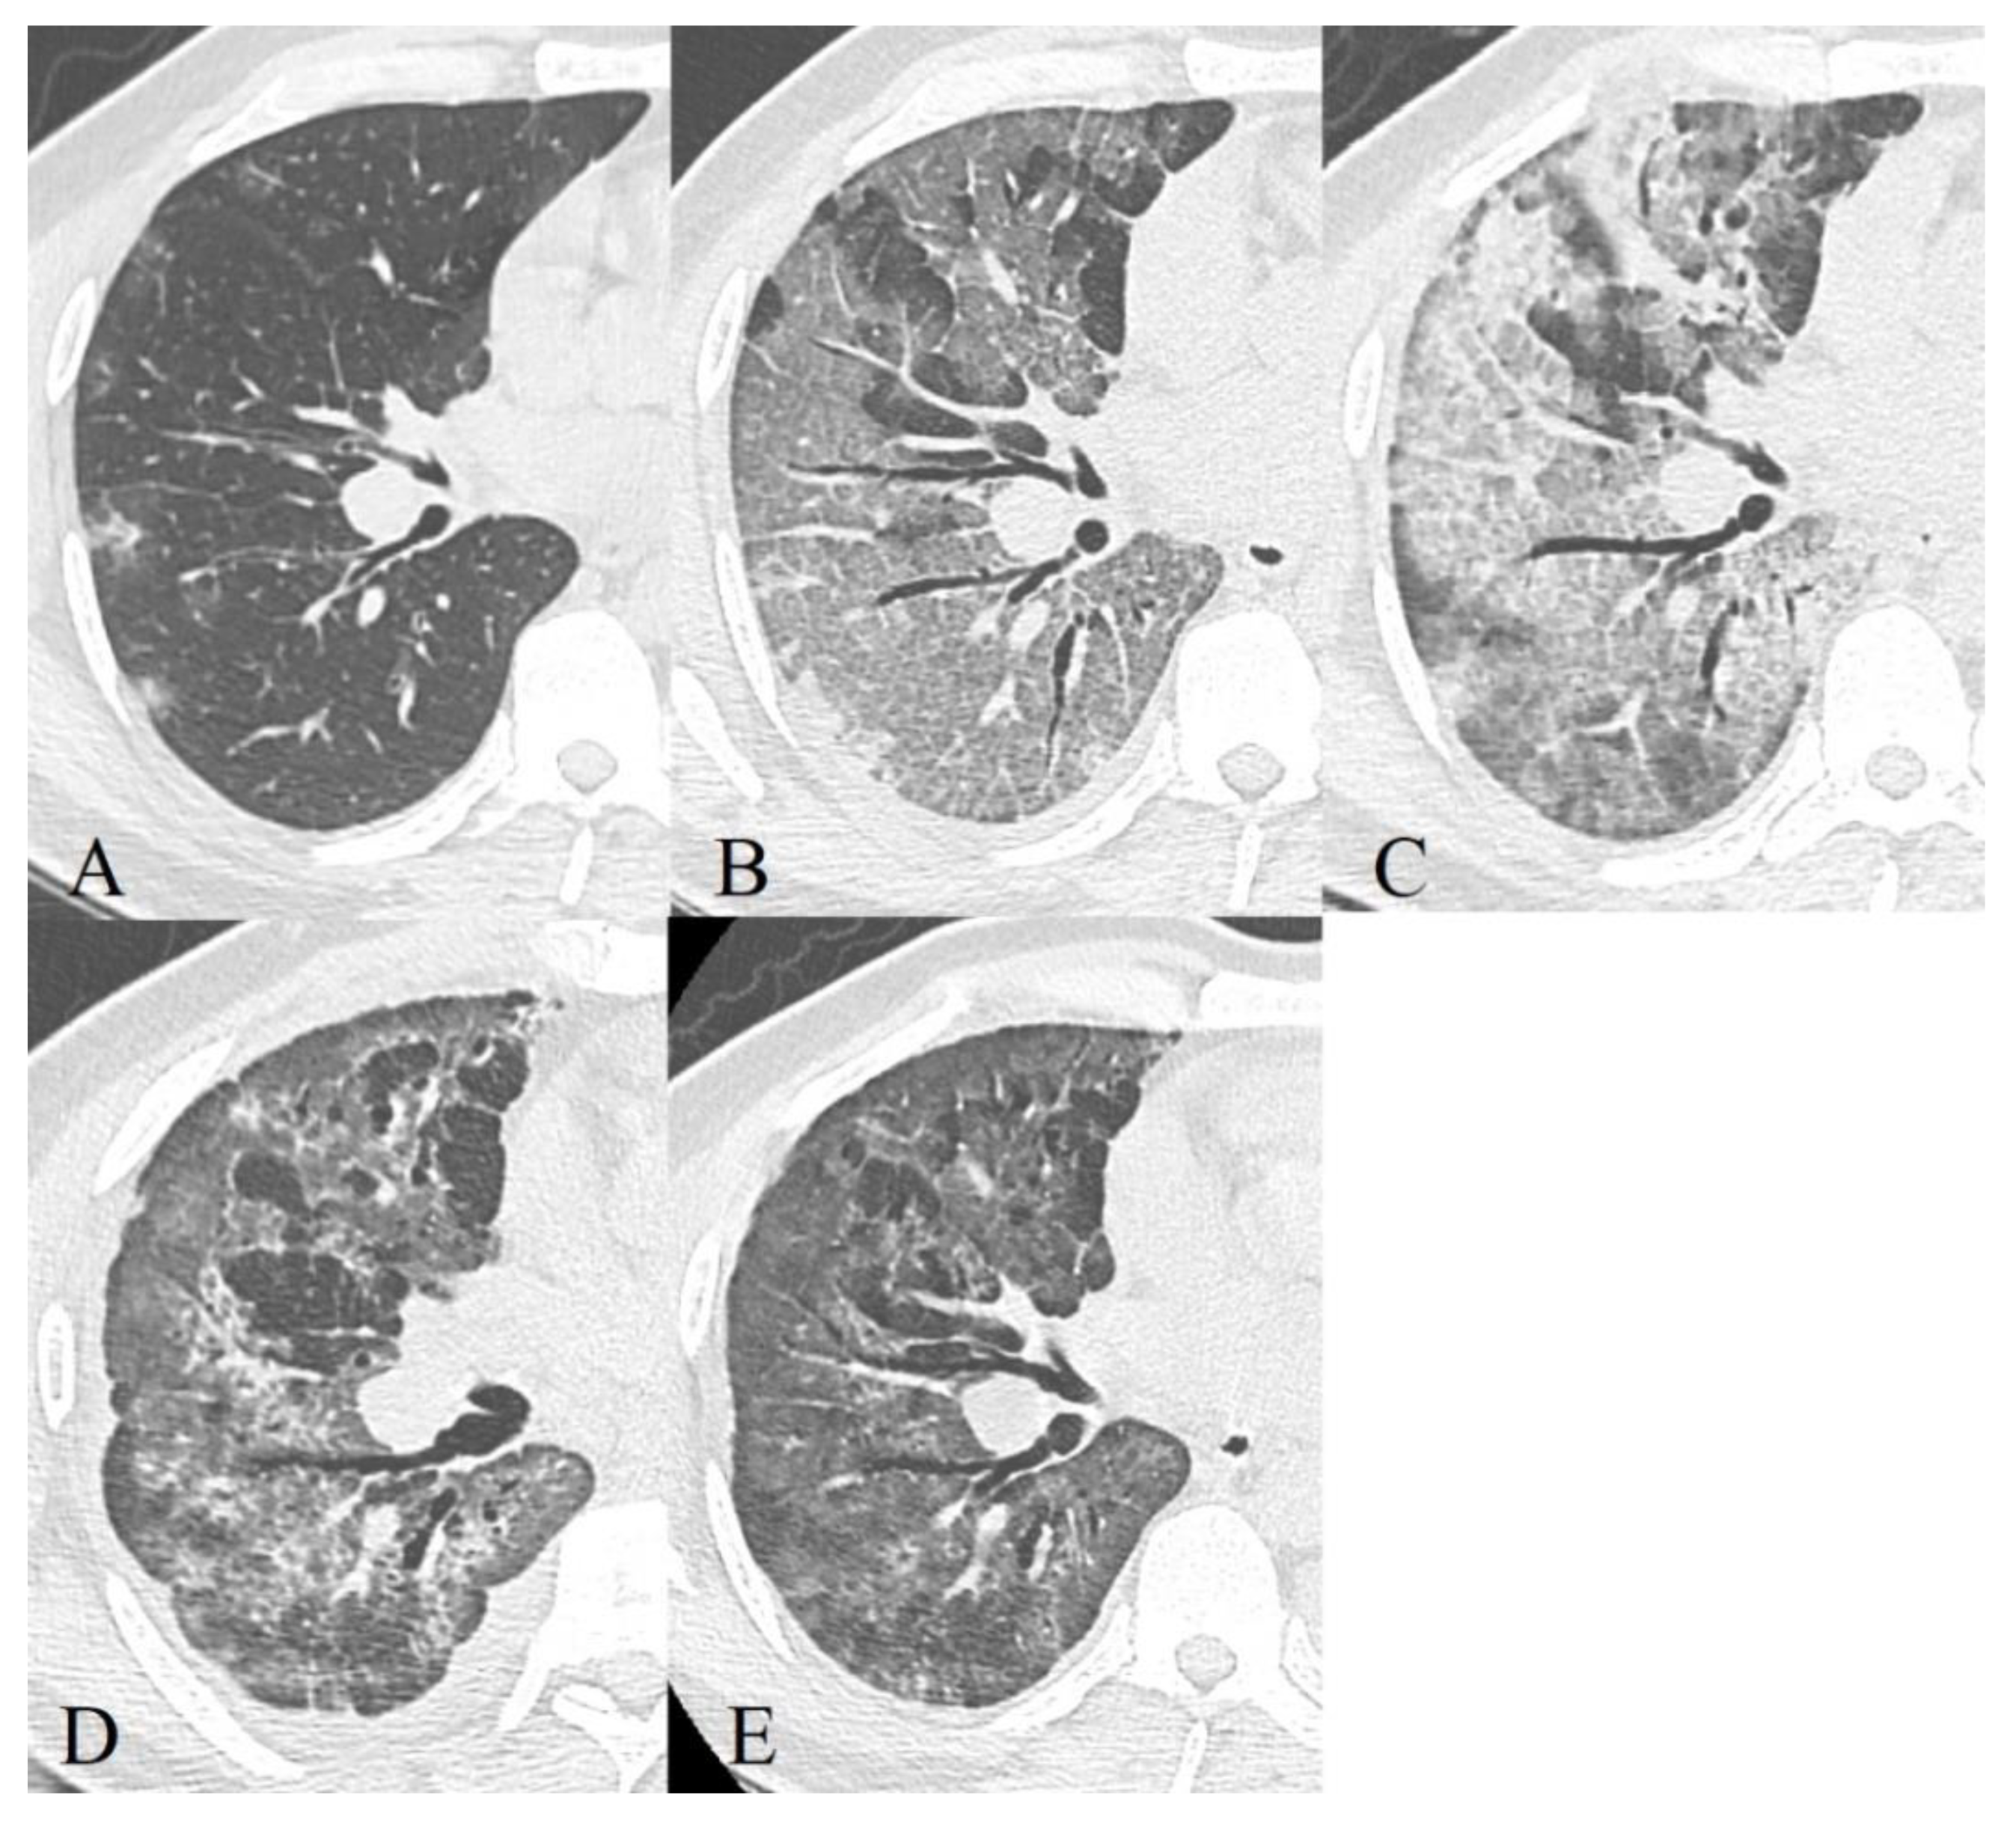

3.2. CT Manifestations of Coronavirus Infection

- Early or initial (0–4 days): GGO type changes dominated in both cohorts, but almost 67% of deceased CT studies had CP pattern in this phase of disease, almost half of studies demonstrated mixed GGO-consolidation changes;

- Progressive (5–8 days): an increase in the volume of the GGO, appearance and increase CP (56% of recovered patient’s studies, 73%—deceased), consolidations (57% of recovered patient’s studies, 87%—deceased) type lesions in both cohorts, RC presented in half of the studies;

- Peak (9–13 days): predominance of a combination of GGO (87%), consolidations (67%), and RC (54%) in recovered patients and the combination of CP (87%), consolidations (77%) and RC (65%)—in deceased. RC demonstrated ascending trend in both cohorts, consolidations—in recovered patients, CP—in deceased, the contribution of GGO decreased in both;

- Resolution (>14 days): predominant contribution of consolidations and RC in both cohorts, at the same time there is a decrease in the contribution of GGO, but CP contribution decreased more slowly in deceased than in recovered patients.